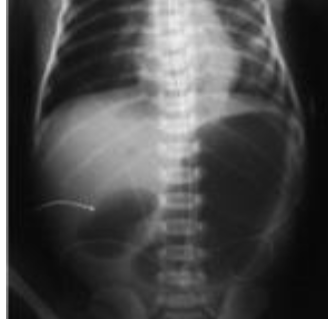

- The abdominal X-ray shows a hyper-lucent shadow separating the liver - (1 from the abdominal wall. This represents free air in the abdomen .which results from intestinal perforation (pneumoperitoneum)

- .The cause of perforation is early and rapid feeding after cardiac arrest - (2 .Intestinal ischemia after cardiac arrest needs time to resolve

- This complication can be prevented by delaying the feed till 7 days elapse - (3 .from the arrest and upgrading the feed gradually